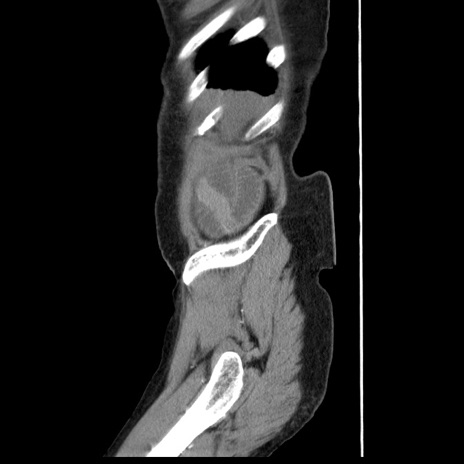

横断像